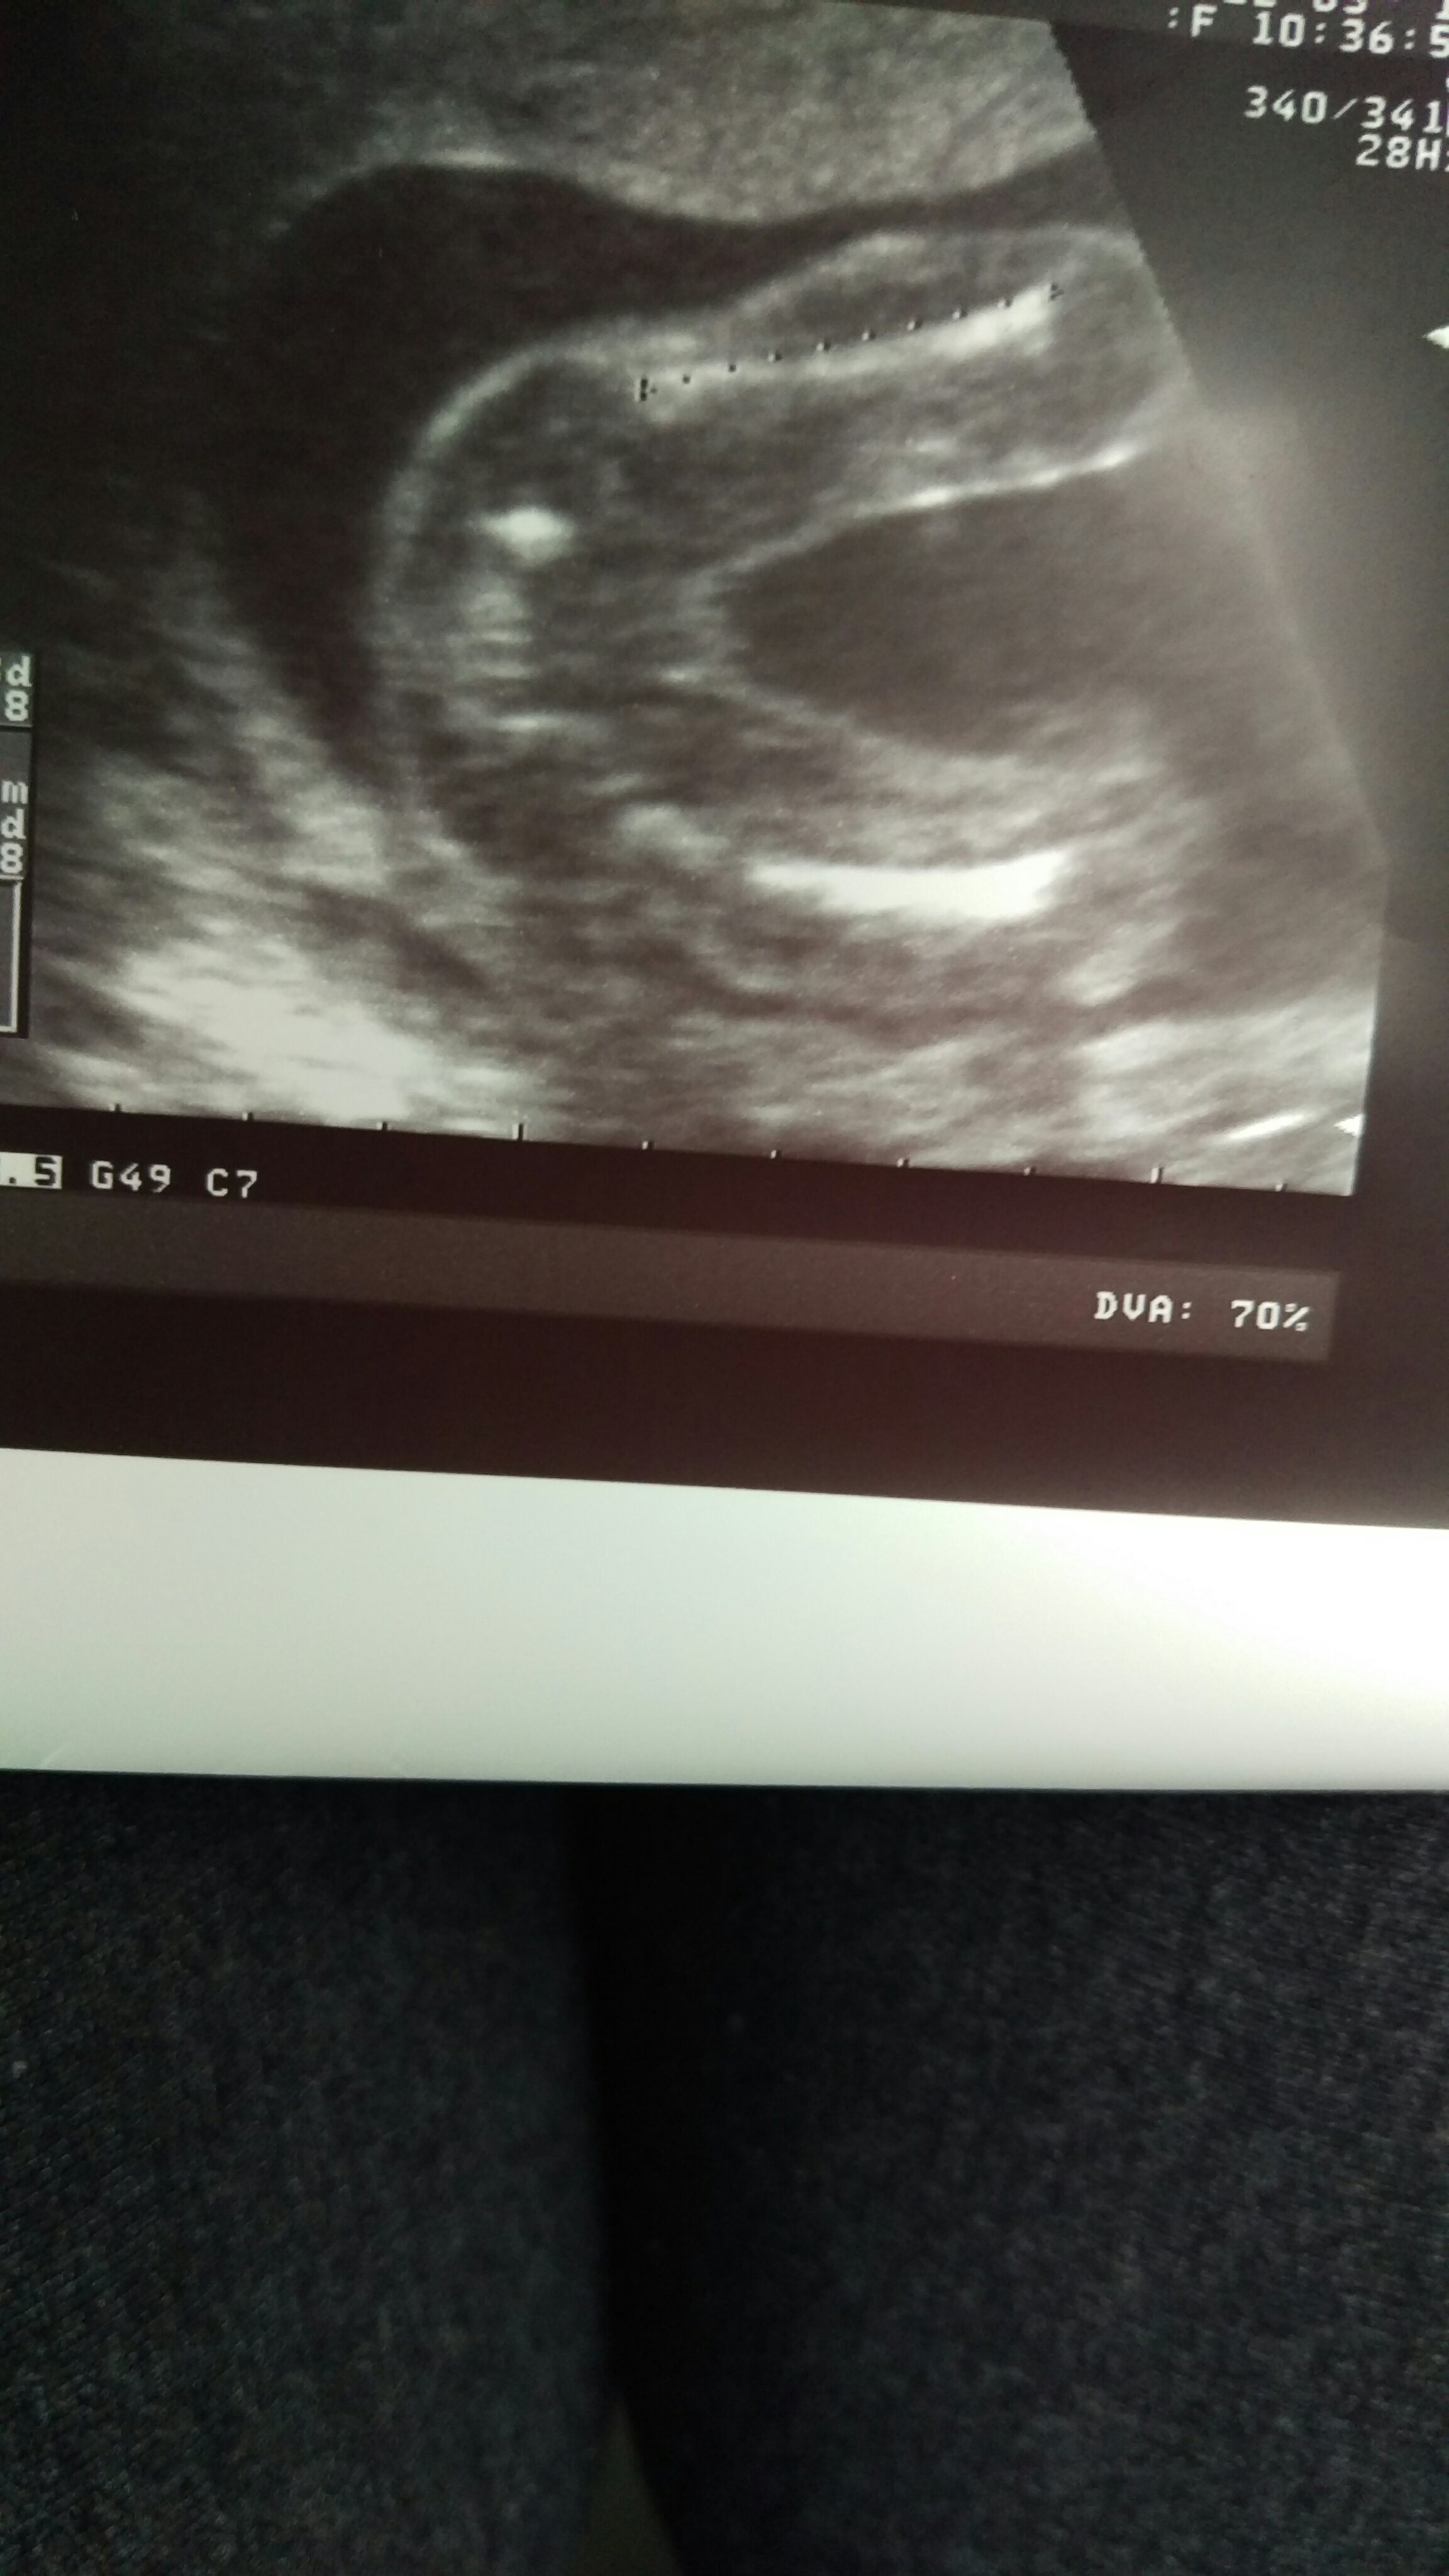

No i po połówkowym:) dzidek zdrowy idealnie:) no i chlopak będzie więc teraz zadanie dla córki wymyśleć imie:))